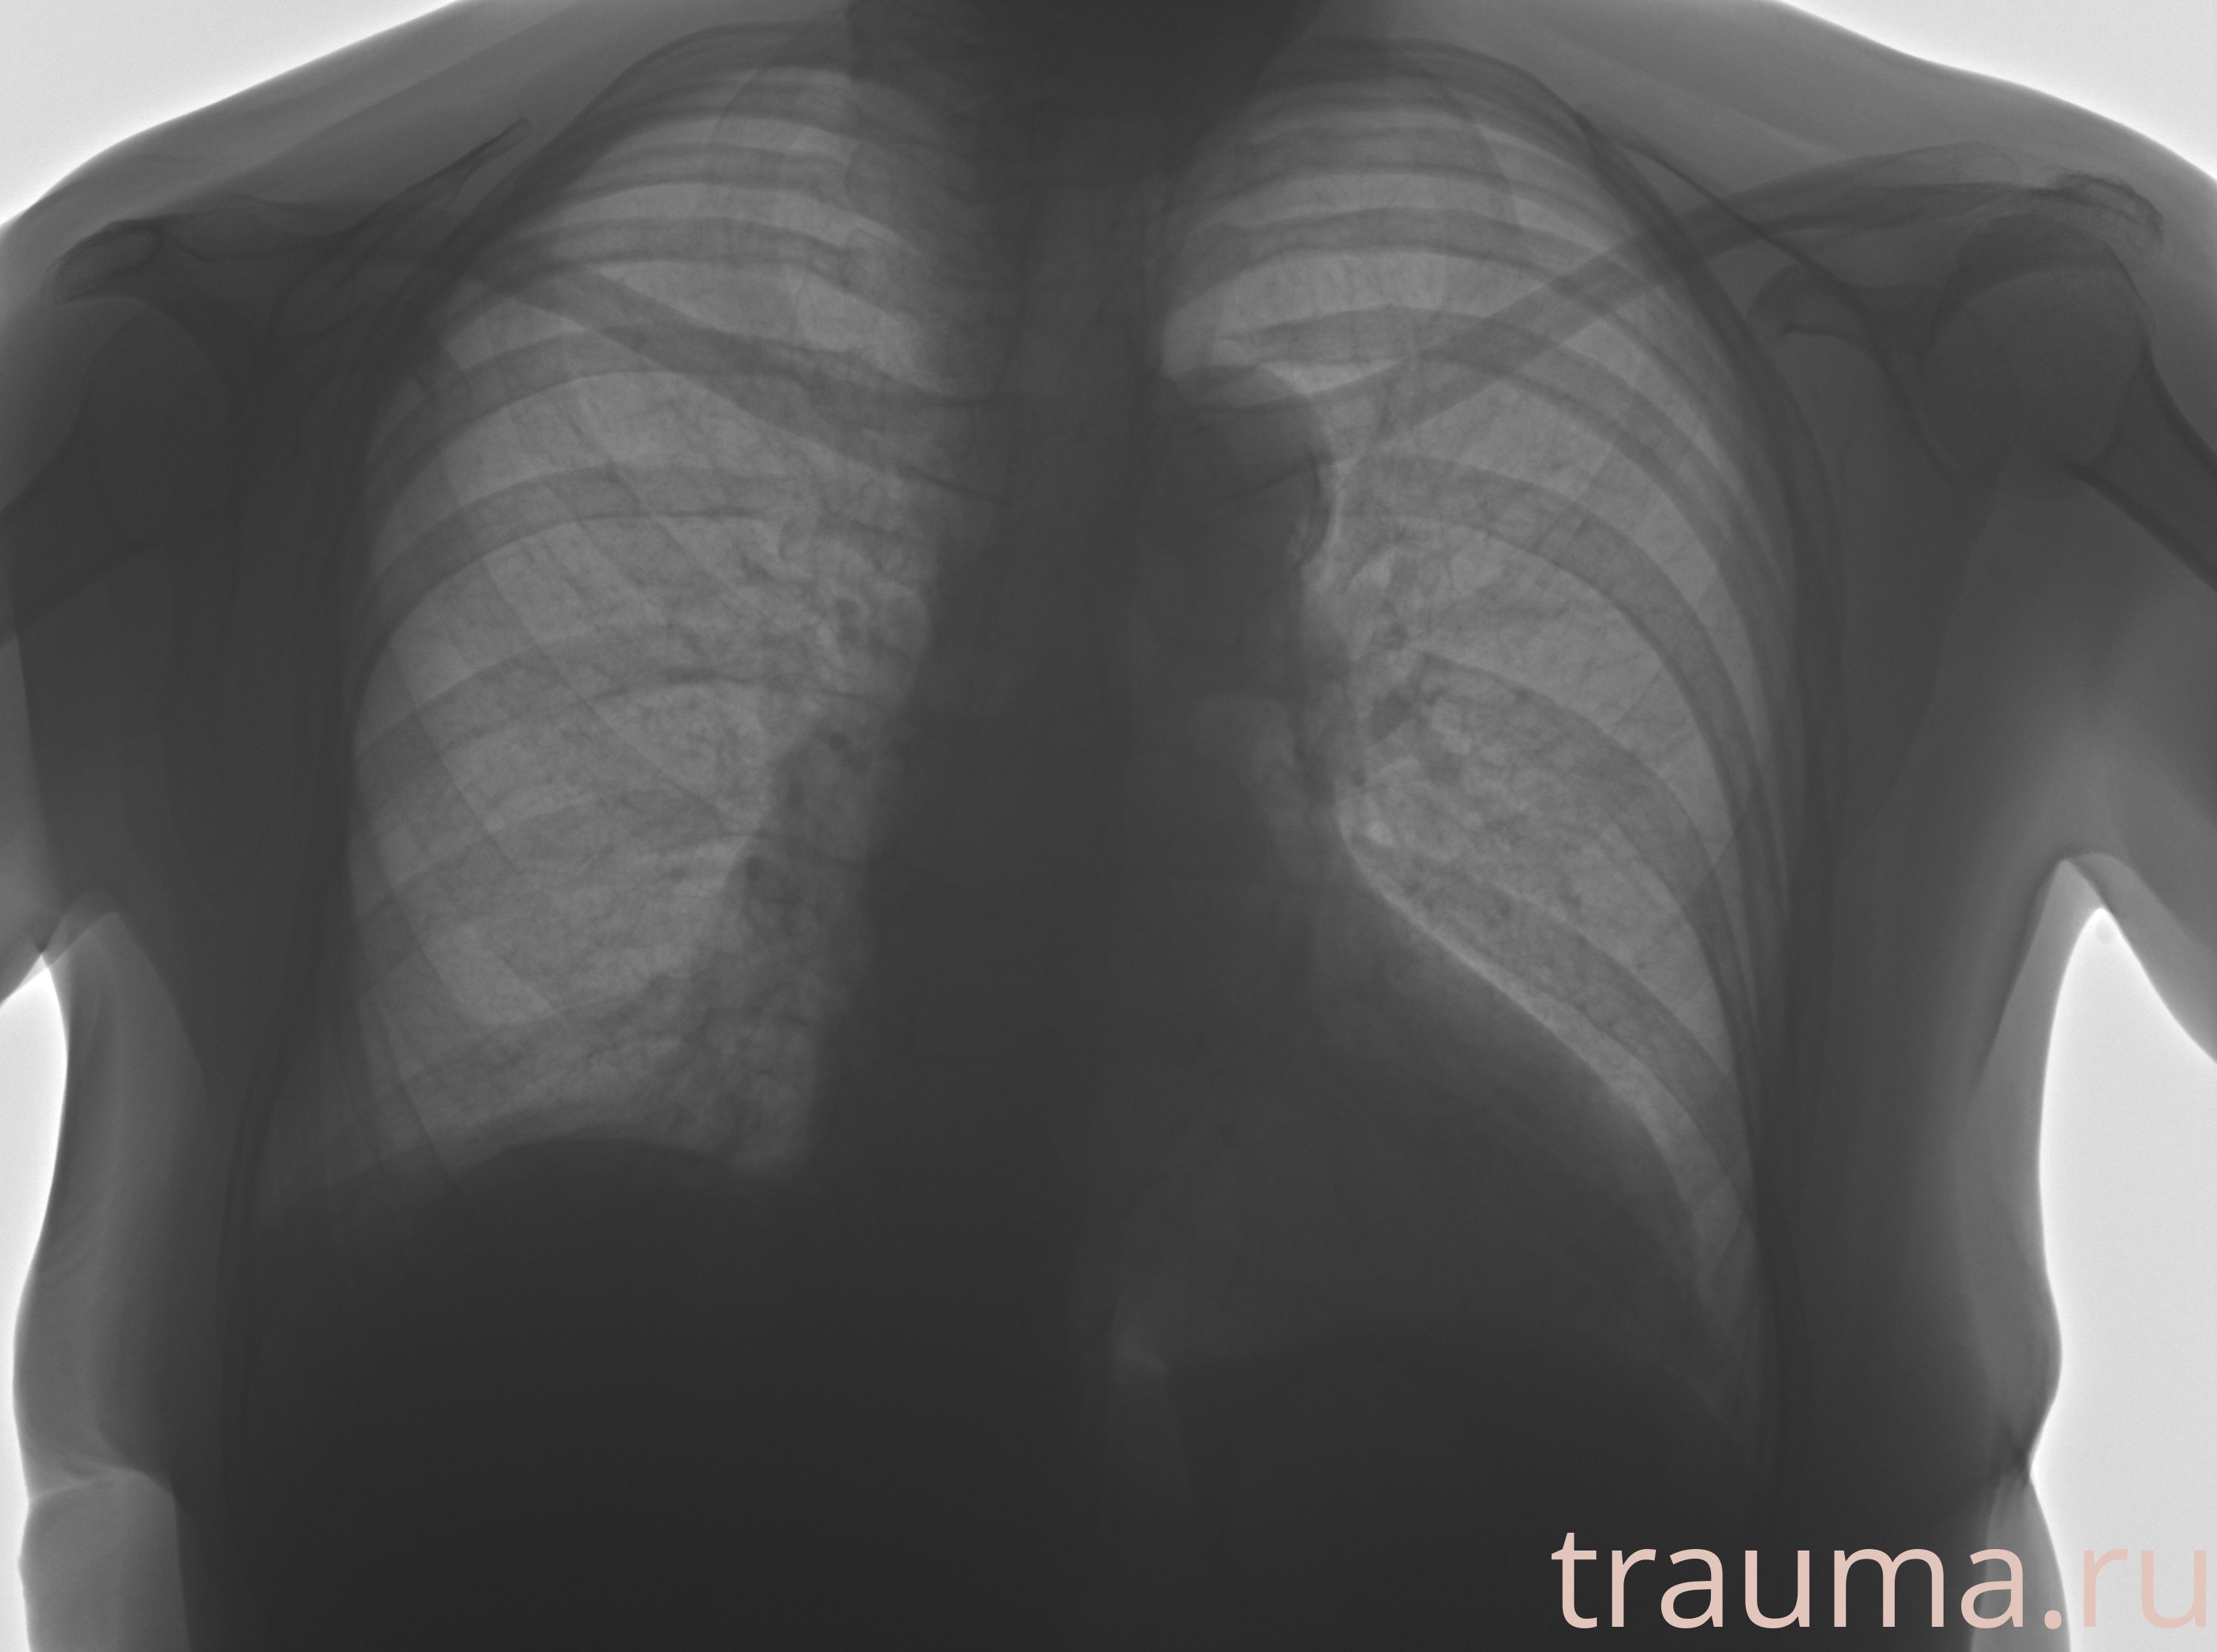

Рентген на дому: по вашему адресу приезжает врач-рентгенолог, травматолог-ортопед с мобильным рентгеновским аппаратом, проводит диагностику травмы или заболевания, делает необходимые рентгенограммы, дает рекомендации по дальнейшему лечению. Получить качественные снимки в домашних условиях возможно благодаря уникальной методике, разработанной МосРентген Центром для института  Склифосовского

при переломе шейки бедра и пневмонии от компании МосРентген Центр - партнера Института имени Склифосовского